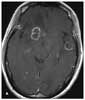

A 47-year-old Hispanic woman with severe headaches of 1 month’s duration presents to the emergency department (ED). The pain encompasses the entire head, is constant and crushing (10 on a scale of 1 to 10), and has progressively worsened. Over-the-counter NSAIDs have provided no relief. She also reports associated photophobia, nausea, and vomiting that interfere with her daily activities, as well as night sweats, fever, and a 15-lb weight loss during the past month. For the past 3 days, she has had left-sided weakness that has reduced her ability to walk or hold a cup in her left hand. An MRI scan obtained 1 week before presentation at the ED showed multiple ring-enhancing lesions with impending uncal herniation (A).